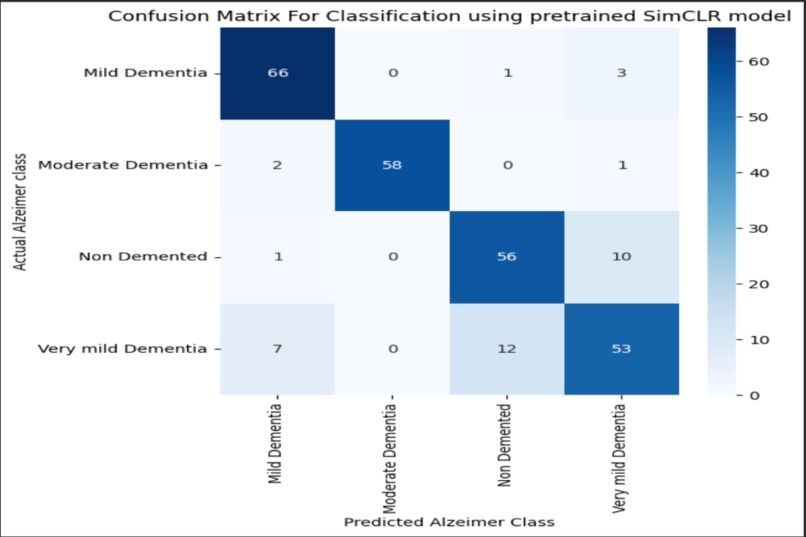

Confusion Matrix for Alzheimers